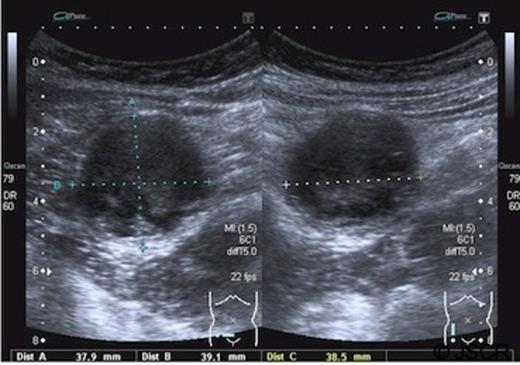

An eleven year old boy presented to the accident and emergency department complaining of pain in the lower abdomen. Initially his signs and symptoms were felt to be consistent with a non-specific cause. He re-presented a week later with persistent localised pain in the right iliac fossa and was noted to have a tender palpable mass, suggestive of appendicular pathology. A full blood count and C-reactive protein were normal. An ultrasound revealed a cystic lesion measuring 38mm by 39mm by 38mm in the right iliac fossa containing complex debris. The wall of the cyst appeared to be multilayered, possibly consistent with a duplication cyst. The appendix was not visualised.(Figure 1)

Ultrasound images showing a spherical cystic lesion with layering within